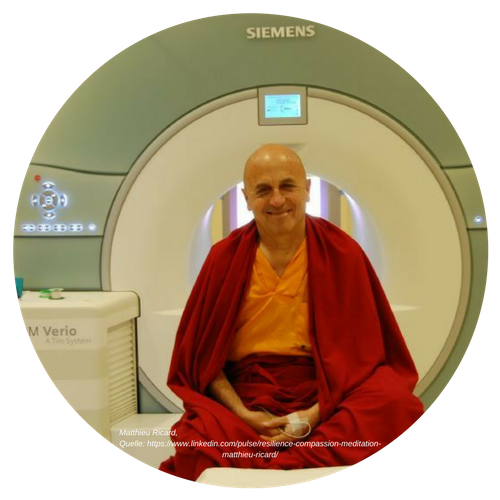

Achtsamkeit ist eine Praxis

Auf diesem Bild ist der meditationserfahrene, buddhistische Mönch und promovierte Molekularbiologe Matthieu Ricard zu sehen. Er wurde in den Gazetten als der glücklichste Mensch der Welt bezeichnet, da die Untersuchungen an seinem Gehirn das nahe legen. Wir müssen keine Mönche werden, um von diesen Erkenntnissen zu profitieren. Es reicht, wenn wir einfach üben. Ricard sieht im Üben von Achtsamkeit und Meditation ein spezielles mentales Training. Er bezeichnet es auch als Geistesschulung.